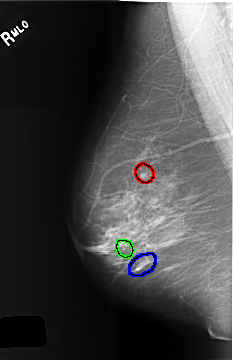

FILE: C_0508_1.RIGHT_MLO.OVERLAY

TOTAL_ABNORMALITIES 3

ABNORMALITY 1

LESION_TYPE MASS SHAPE ROUND MARGINS CIRCUMSCRIBED

ASSESSMENT 2

SUBTLETY 5

PATHOLOGY BENIGN_WITHOUT_CALLBACK

TOTAL_OUTLINES 1

BOUNDARY

ABNORMALITY 2

LESION_TYPE CALCIFICATION TYPE PLEOMORPHIC DISTRIBUTION CLUSTERED

ASSESSMENT 3

PATHOLOGY BENIGN

ABNORMALITY 3

ASSESSMENT 4

TOTAL_OUTLINES 2